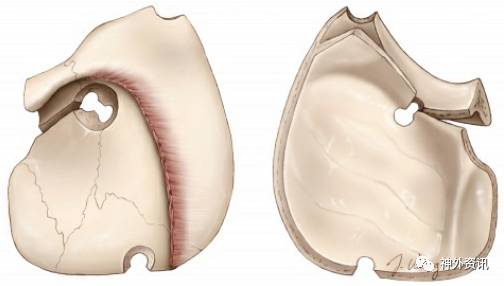

图5:改良眶颧入路移除的骨质包括眶缘、眶顶前部及颧骨额突的一部分。骨质切割范围可延伸至眶下裂,但已很少应用。额颧缝(蓝箭)大约为眶顶水平(感谢Rhoton教授对图片的授权)。

图6:与眶颧入路相关的前外侧颅底的骨性解剖(左上图)。注意从眶内侧面观察到的关键孔与额颧缝的关系(上右图和下左图)。翼点入路中的“关键孔”则位于眶颧入路中的McCarty关键孔的上方,前者仅需暴露额叶硬膜,而后者需同时暴露眶骨膜和额叶硬膜(感谢Rhoton教授对图片的授权)。

图7:关键孔周围的骨缝解剖(左上图)。本人研究发现,为同时显露眶骨膜以及被眶顶隔开的额叶硬膜,最佳的关键孔定位为A1点(右上图)(此处与所引原文观点不同;原文中Rhoton等作者认为最佳定位点为B1;译者注)。注意眶顶与垂直虚线之间呈一夹角(左下图)。眶顶的厚度和倾斜角度存在变异。需熟悉其典型的倾斜角度,以便在术中保证关键孔能同时暴露额叶硬膜和眶骨膜(感谢Rhoton教授对图片的授权)。

图8:对这一起始关键孔的精准定位,以同时暴露眶骨膜和额叶硬膜,是之后顺利完成眶颧和眶上/额眶骨切开术的关键步骤。该孔的中心通常位于额颧缝(黑箭)上方7mm、后方5mm的位置。